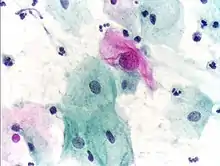

_Smear.jpg.webp) Micrograph of a normal pap smear

Micrograph of a normal pap smear Micrograph of a Pap test showing a low-grade intraepithelial lesion (LSIL) and benign endocervical mucosa. Pap stain.